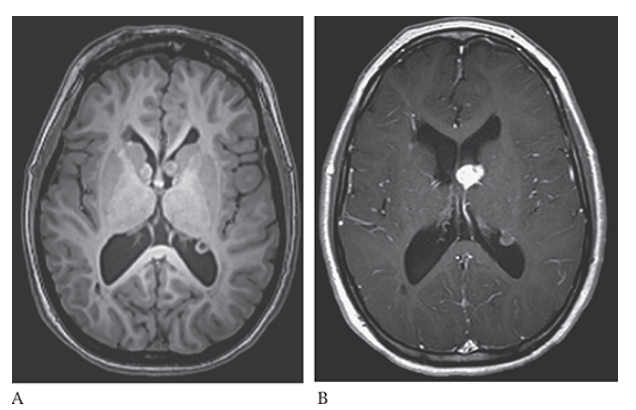

What is A

Tuberous Sclerosis. PD axial and postcontrast T1W

What is B

Tuberous Sclerosis. PD axial contrast shows an enhancing left subependymal giant cell astrocytoma in the foramen of Monroe and an enhancing subependymal nodule in the trigone of the left lateral ventricle.